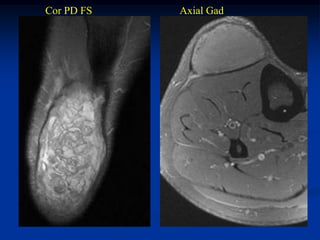

Case #251.1                   Desmoid tumor of foot

10 year male with firm tender swelling in forefoot 18 mos

following a pellet gun injury to foot

Cor T-1   T-2   Gad

Sag T-1

Gad

Axial T-1   T-2